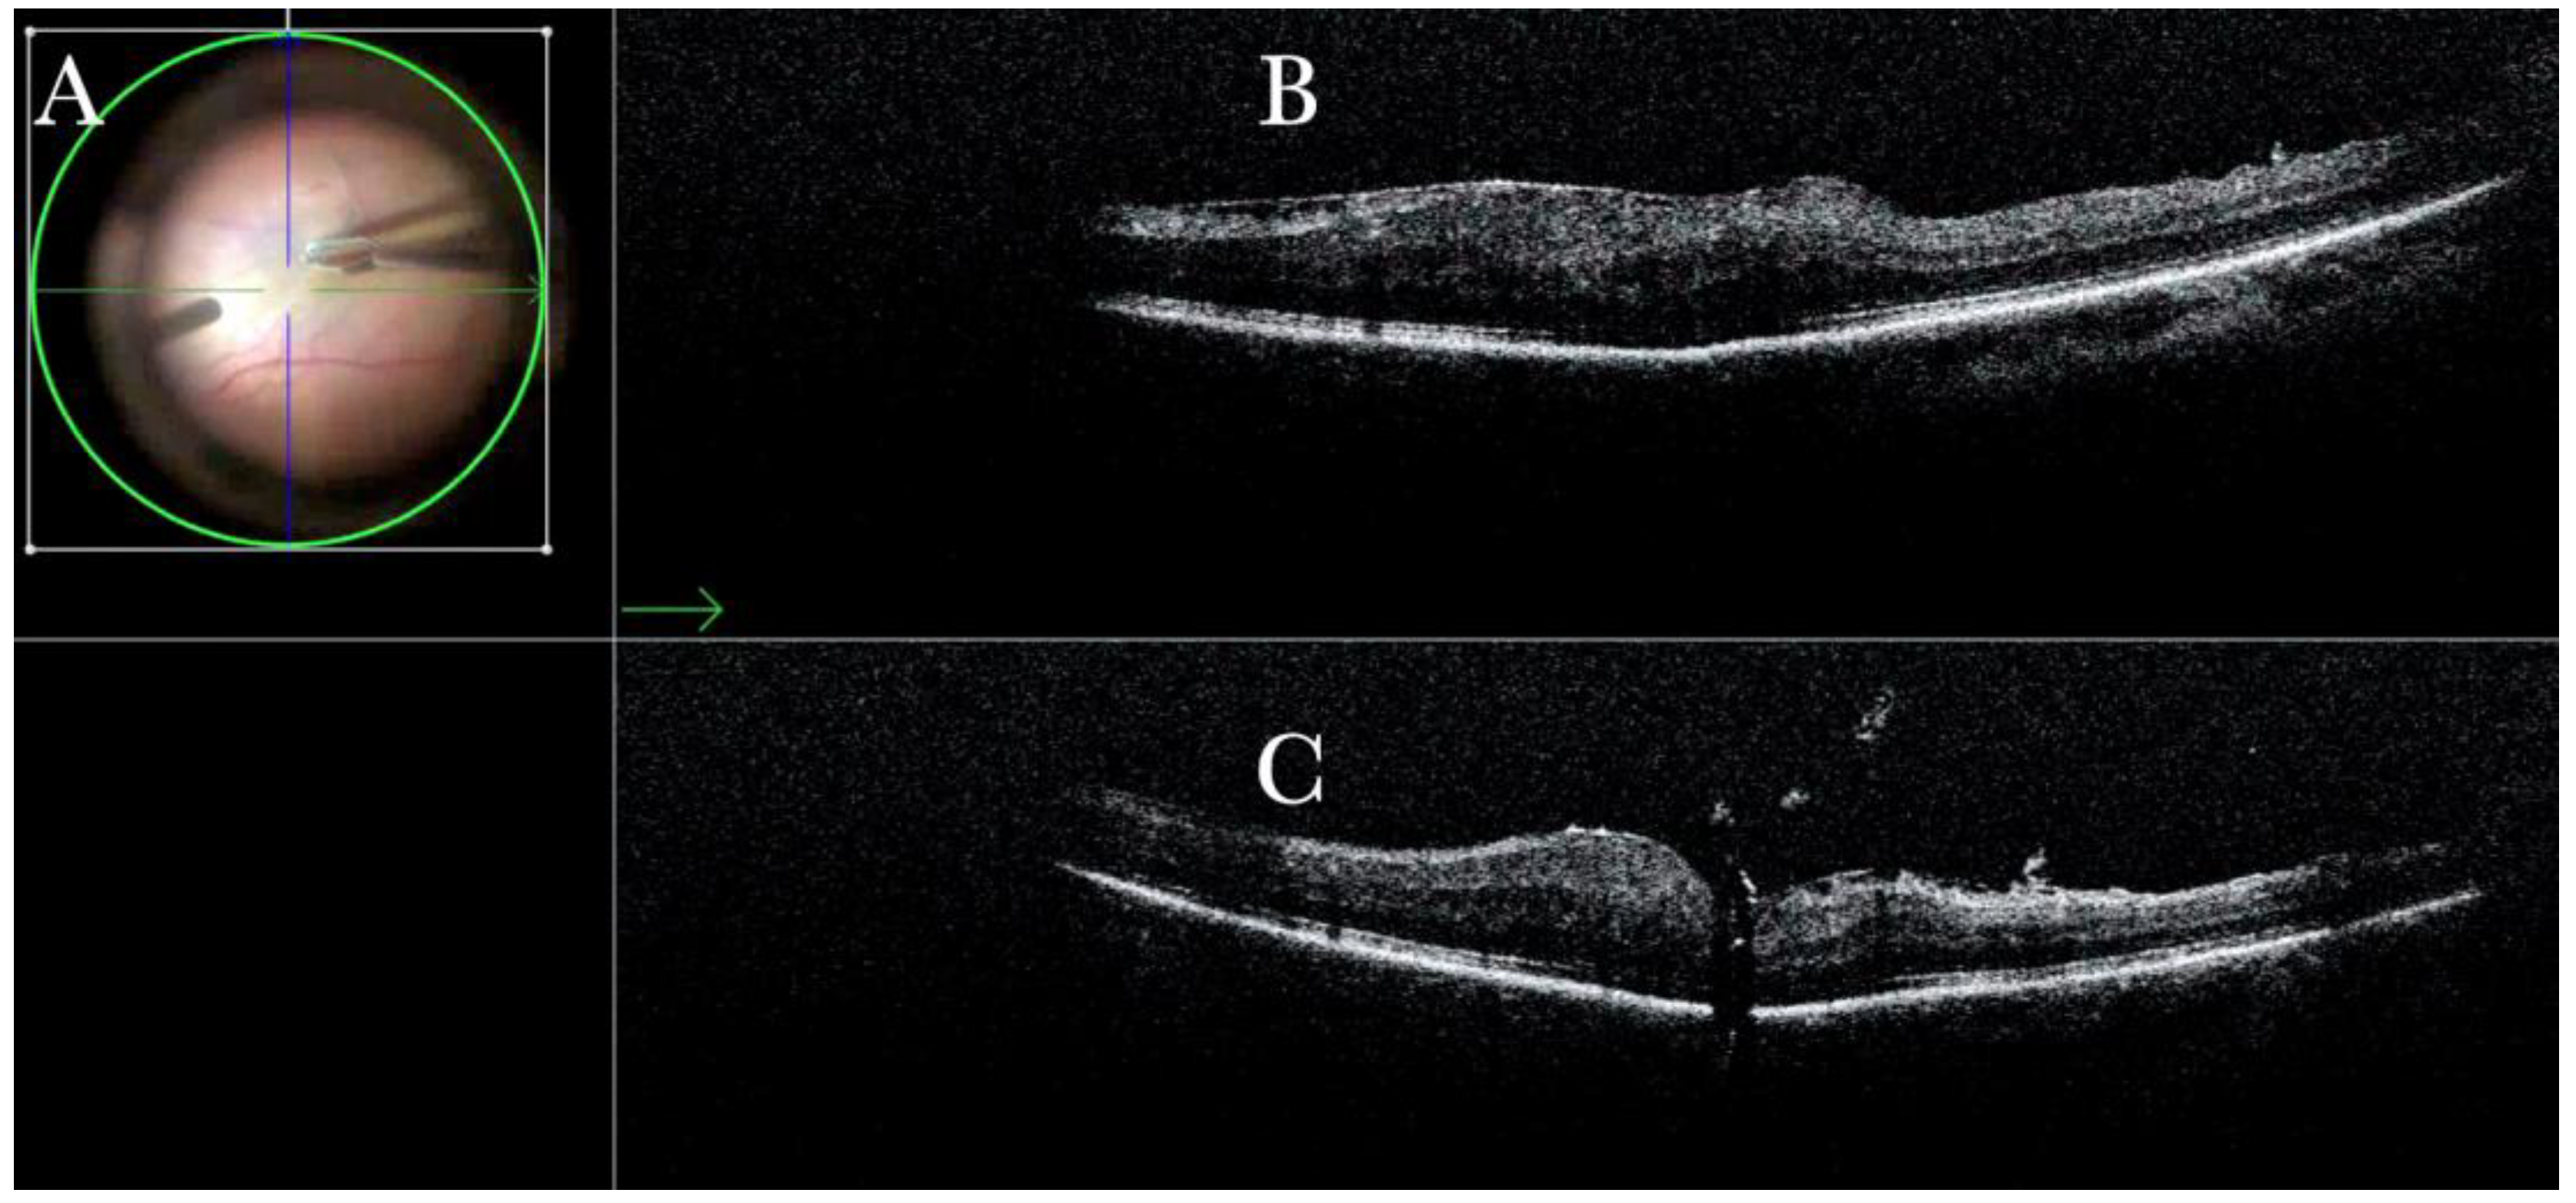

Figure 11.

(A) Microscope view of the macular area in case of myopic traction maculopathy in stage 4C (macular detachment with full-thickness macular hole (FTMH)) after implanting a macular buckle. The transillumination of a fiber optic inserted into the buckle allows us to guess the location of the buckle itself. The inner limiting membrane (ILM) flap is visibly stained blue. The FTMH is not visible. (The white box indicates the field-of-view of the OCT scan, the green line within the green box shows the scan plane) (B) The Intraoperative Optical coherence tomography (i-OCT) B horizontal (green arrow) and vertical scan shows very clearly the indentation of the macula from the scleral side due to the presence of a macular buckle. The white arrowhead shows the FTMH, which is not over the buckle. (C) Same view as in A after repositioning the macular buckle. (The white box indicates the field-of-view of the OCT scan, the green line within the green box shows the scan plane) (D) i-OCT B horizontal (green arrow) and vertical scan showing very clearly the indentation of the macula from the scleral side due to the presence of a macular buckle. The white arrow shows the FTMH, which is now well-positioned over the buckle.